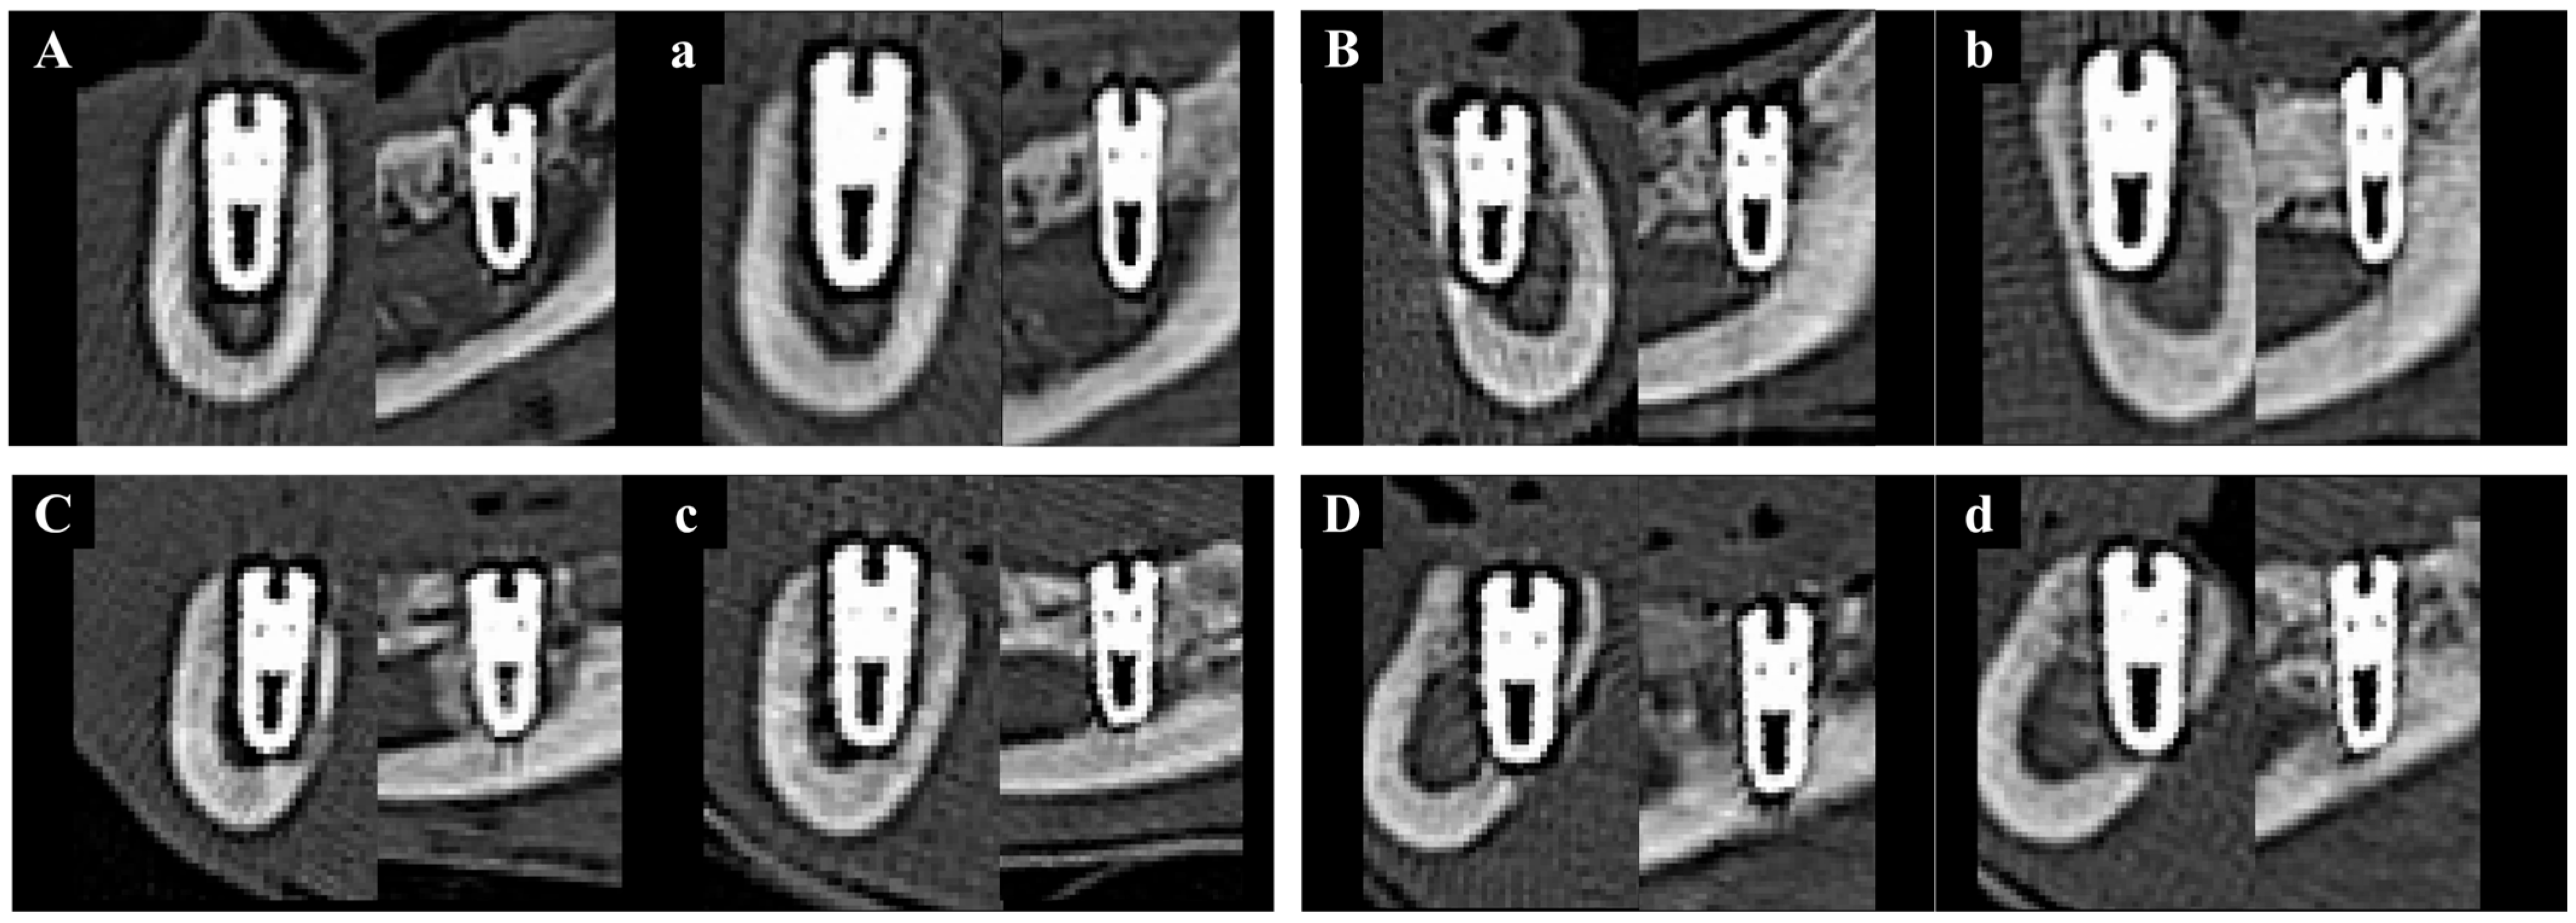

3.2.4. Micro-CT Findings

| Contents | Weeks | Groups | Mean ± SD | p-Value |

| NBV (%) | 8 | NS | 52.87 ± 10.78 a | 0.002 * |

| BS | 64.51 ± 8.33 b | |||

| PS | 65.56 ± 6.22 b,c | |||

| PB | 75.04 ± 6.33 c,d |